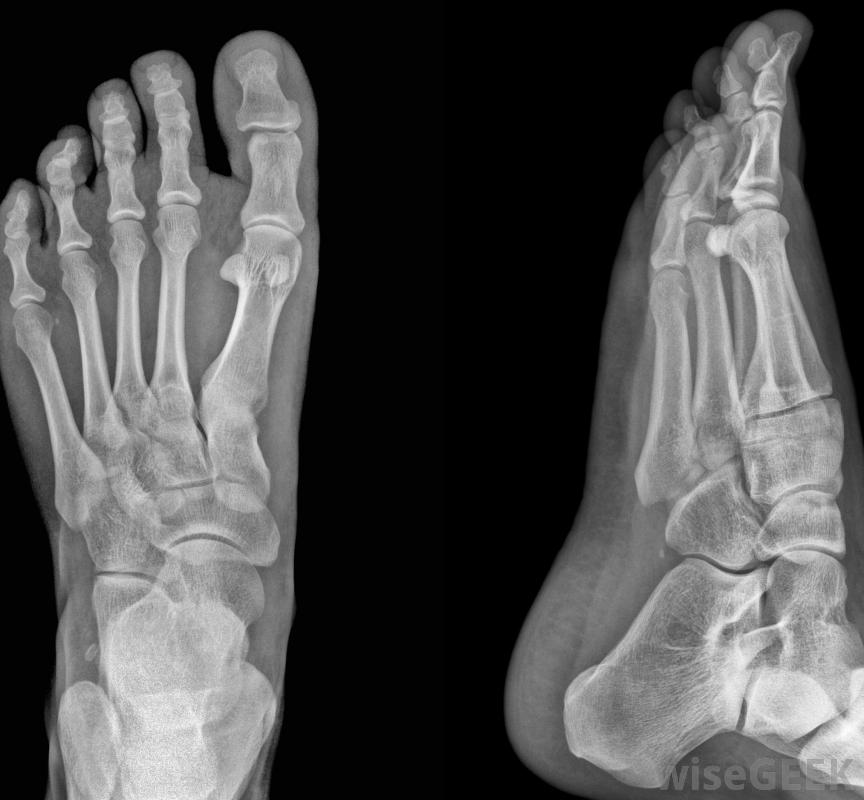

再造脚趾手术是一种旨在恢复足部一个或多个脚趾的活动性或可用性的医疗过程。这种手术可以解决许多不同的医疗问题,从严重的骨折或骨折到关节炎或锤状趾。再造脚趾手术可能只涉及脚趾骨的改变,或者可能包括脚趾骨和足部骨骼的改变,特别是连接脚趾骨和足部其他部位的跖骨。手术后的恢复可能是长期的,而且会有些疼痛。

重建脚趾手术可用于改变脚趾和足部的骨骼。重建脚趾手术的具体过程可能因问题而异例如,锤状趾是指脚趾弯曲,改变脚的稳定性和活动性的一种情况。重建脚趾手术可以切除足部的骨骼,从而使骨骼伸直并正常工作。这可以减轻疼痛,恢复活动性,甚至是解决美容问题。恢复期可能会持续数周,在此期间,患者需要远离足部,并监测受影响的足部是否存在感染或其他问题。

脚趾重建手术的具体过程可能因所处理的问题而异。如果脚趾发生严重骨折,重建脚趾手术可能是必要的,以恢复该脚趾的功能。手术将包括切除一些受损的骨头,在骨头中插入针或钢板,使其与其他骨头保持稳定,并修复任何受损的肌腱或肌肉患者可能会也可能不会从这种手术中完全恢复;很可能脚趾的活动性会因为钉和钢板而降低,而且脚趾的柔韧性也可能大大降低。脚趾缩短是另一种重建脚趾的手术。有些人的脚趾拉长,会改变平衡、活动能力或仅仅是美观。如果脚趾导致疼痛或不适,重建脚趾手术可以使组成脚趾的一块或多块骨头基本上变短。切割骨头通常在关节处进行,也可以在靠近跖骨的地方进行。这是一种相对安全的手术,虽然恢复时间长达三个月,但也有可能出现并发症。一些最常见的并发症包括活动能力下降、神经损伤、刺痛,甚至脚趾感觉丧失。